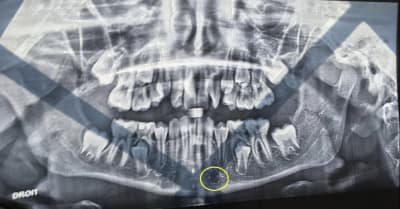

D'ordinaire, les agénésies incisives inférieures, c'est plutôt 31 ou 41 ou plus souvent souvent les 2.

C'est quoi ce truc sur la pano, un artéfact ?

Ce doit être un reflet de sa fenêtre sur l’écran de son ordi lors de de la photo.

Un reflet de fenêtre, ça ne ressemble pas à ça…

21/06/2019 à 10h38

C'est pas tout simplement le foramen mentonnier sur la radio? Vrai qu'il semble un peu en avant mais c'est à çà que çà me fait penser!